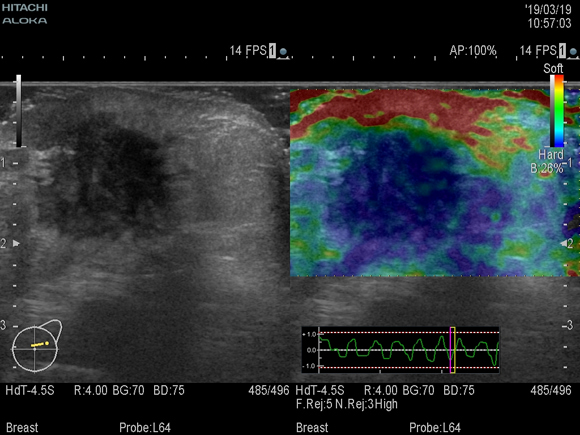

乳腺・甲状腺エコー

超音波を用いて、乳房内や甲状腺内の病変の有無、存在部位、大きさ、性状の評価並びに薬物療法の治療評価を行います。

乳腺が発達している若い女性は、マンモグラフィだけでは診断が難しいこともあり、エラストグラフィ(超音波組織弾性映像法)なども併用して診断しています。エラストグラフィとは組織の硬さをリアルタイムで画像化する技術です。良性病変に比べてがん組織がより硬いことを利用してがんを検出しています。

(下図)乳腺腫瘍。エラストグラフィでは硬さが色で表されます(硬いほど青く、柔らかいほど赤い)。歪んだ青色の円として浮き彫りに描出されています。